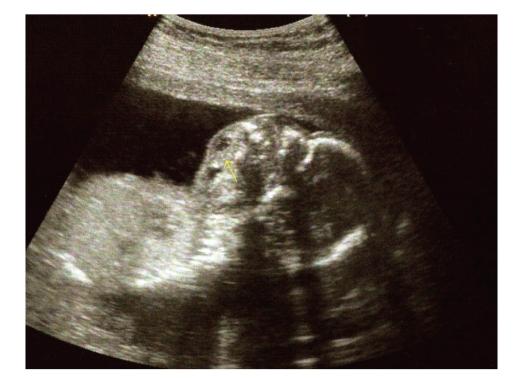

Background. Teratomas are the most common tumors. They are usually localized in the sacrococcygeal area, while the pharyngeal localization is very rare. The number of cases of stomatopharyngeal teratomas detected prenatally via sonography is very small. Case Report. We present the case of a 24-year-old primipara at 18 weeks' gestation, that at the routine ultrasound scan, the fetus was found with an echogenic mass, filling the stomatopharyngeal cavity and protruding from the mouth. Other abnormalities were not found. Termination of pregnancy was achieved using misoprostol. A female stillborn fetus with a weight of 250 g and length of 25.5 cm was delivered. The postmortem and pathologic examination confirmed the diagnosis. Conclusion. Pharyngeal teratomas can be diagnosed with the use of ultrasounds in utero facilitating parents' counseling in early time.

背景。畸胎瘤是最常见的肿瘤。它们通常位于骶尾部区域,而咽部定位非常罕见。产前通过超声检查发现的口咽畸胎瘤病例数量非常少。病例报告。我们报告一例24岁初产妇,妊娠18周,在常规超声检查时,发现胎儿有一个回声团块,充满口咽腔并从口腔突出。未发现其他异常。使用米索前列醇终止妊娠。分娩出一名体重250克、身长25.5厘米的女死胎。尸检和病理检查确诊。结论。子宫内超声检查可诊断咽部畸胎瘤,有助于早期为父母提供咨询。